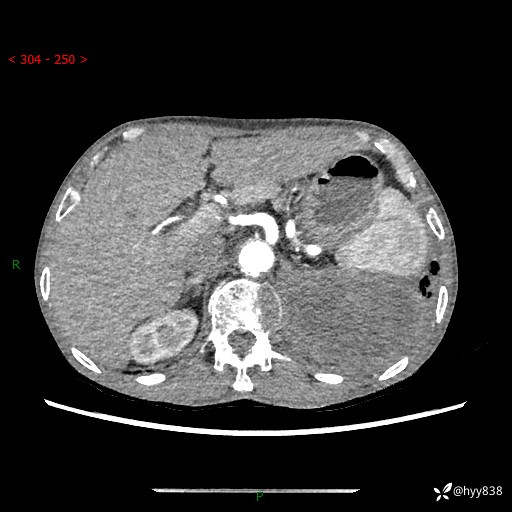

77岁/男,腹痛2月,CT发现左肺占位1天。巨大肿块,肺内或肺外来源…结果公布~

主诉:腹痛2月,CT发现左肺占位1天

现病史:患者于2025年9月间断左下腹胀痛,在当地镇卫生院行彩超检查考虑泌尿系结石,行止痛排石对症治疗未见明显好转;1天前腹痛症状加重,至当地市第三人民医院行CT检查:左肺下叶巨大团块状软组织影,考虑肿瘤性病变,建议增强CT检查;左侧胸腔积液;纵膈内淋巴结肿大;双肺肺气肿;右肺中叶纤维灶。为进一步求治,来我院就诊。

胸部CT平扫+增强